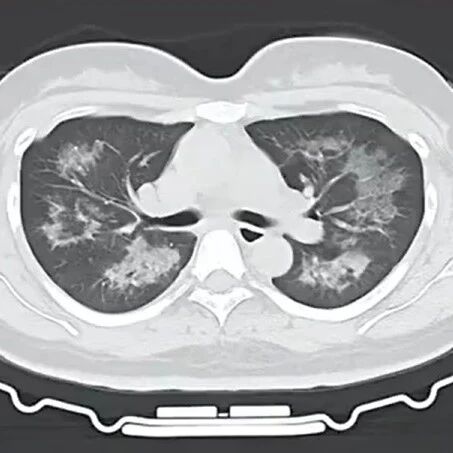

每天用2次,22岁女主播肺里长满阴影!提醒: 很多人不注意 大湘网 · 公众号 · · 2 天前 · |